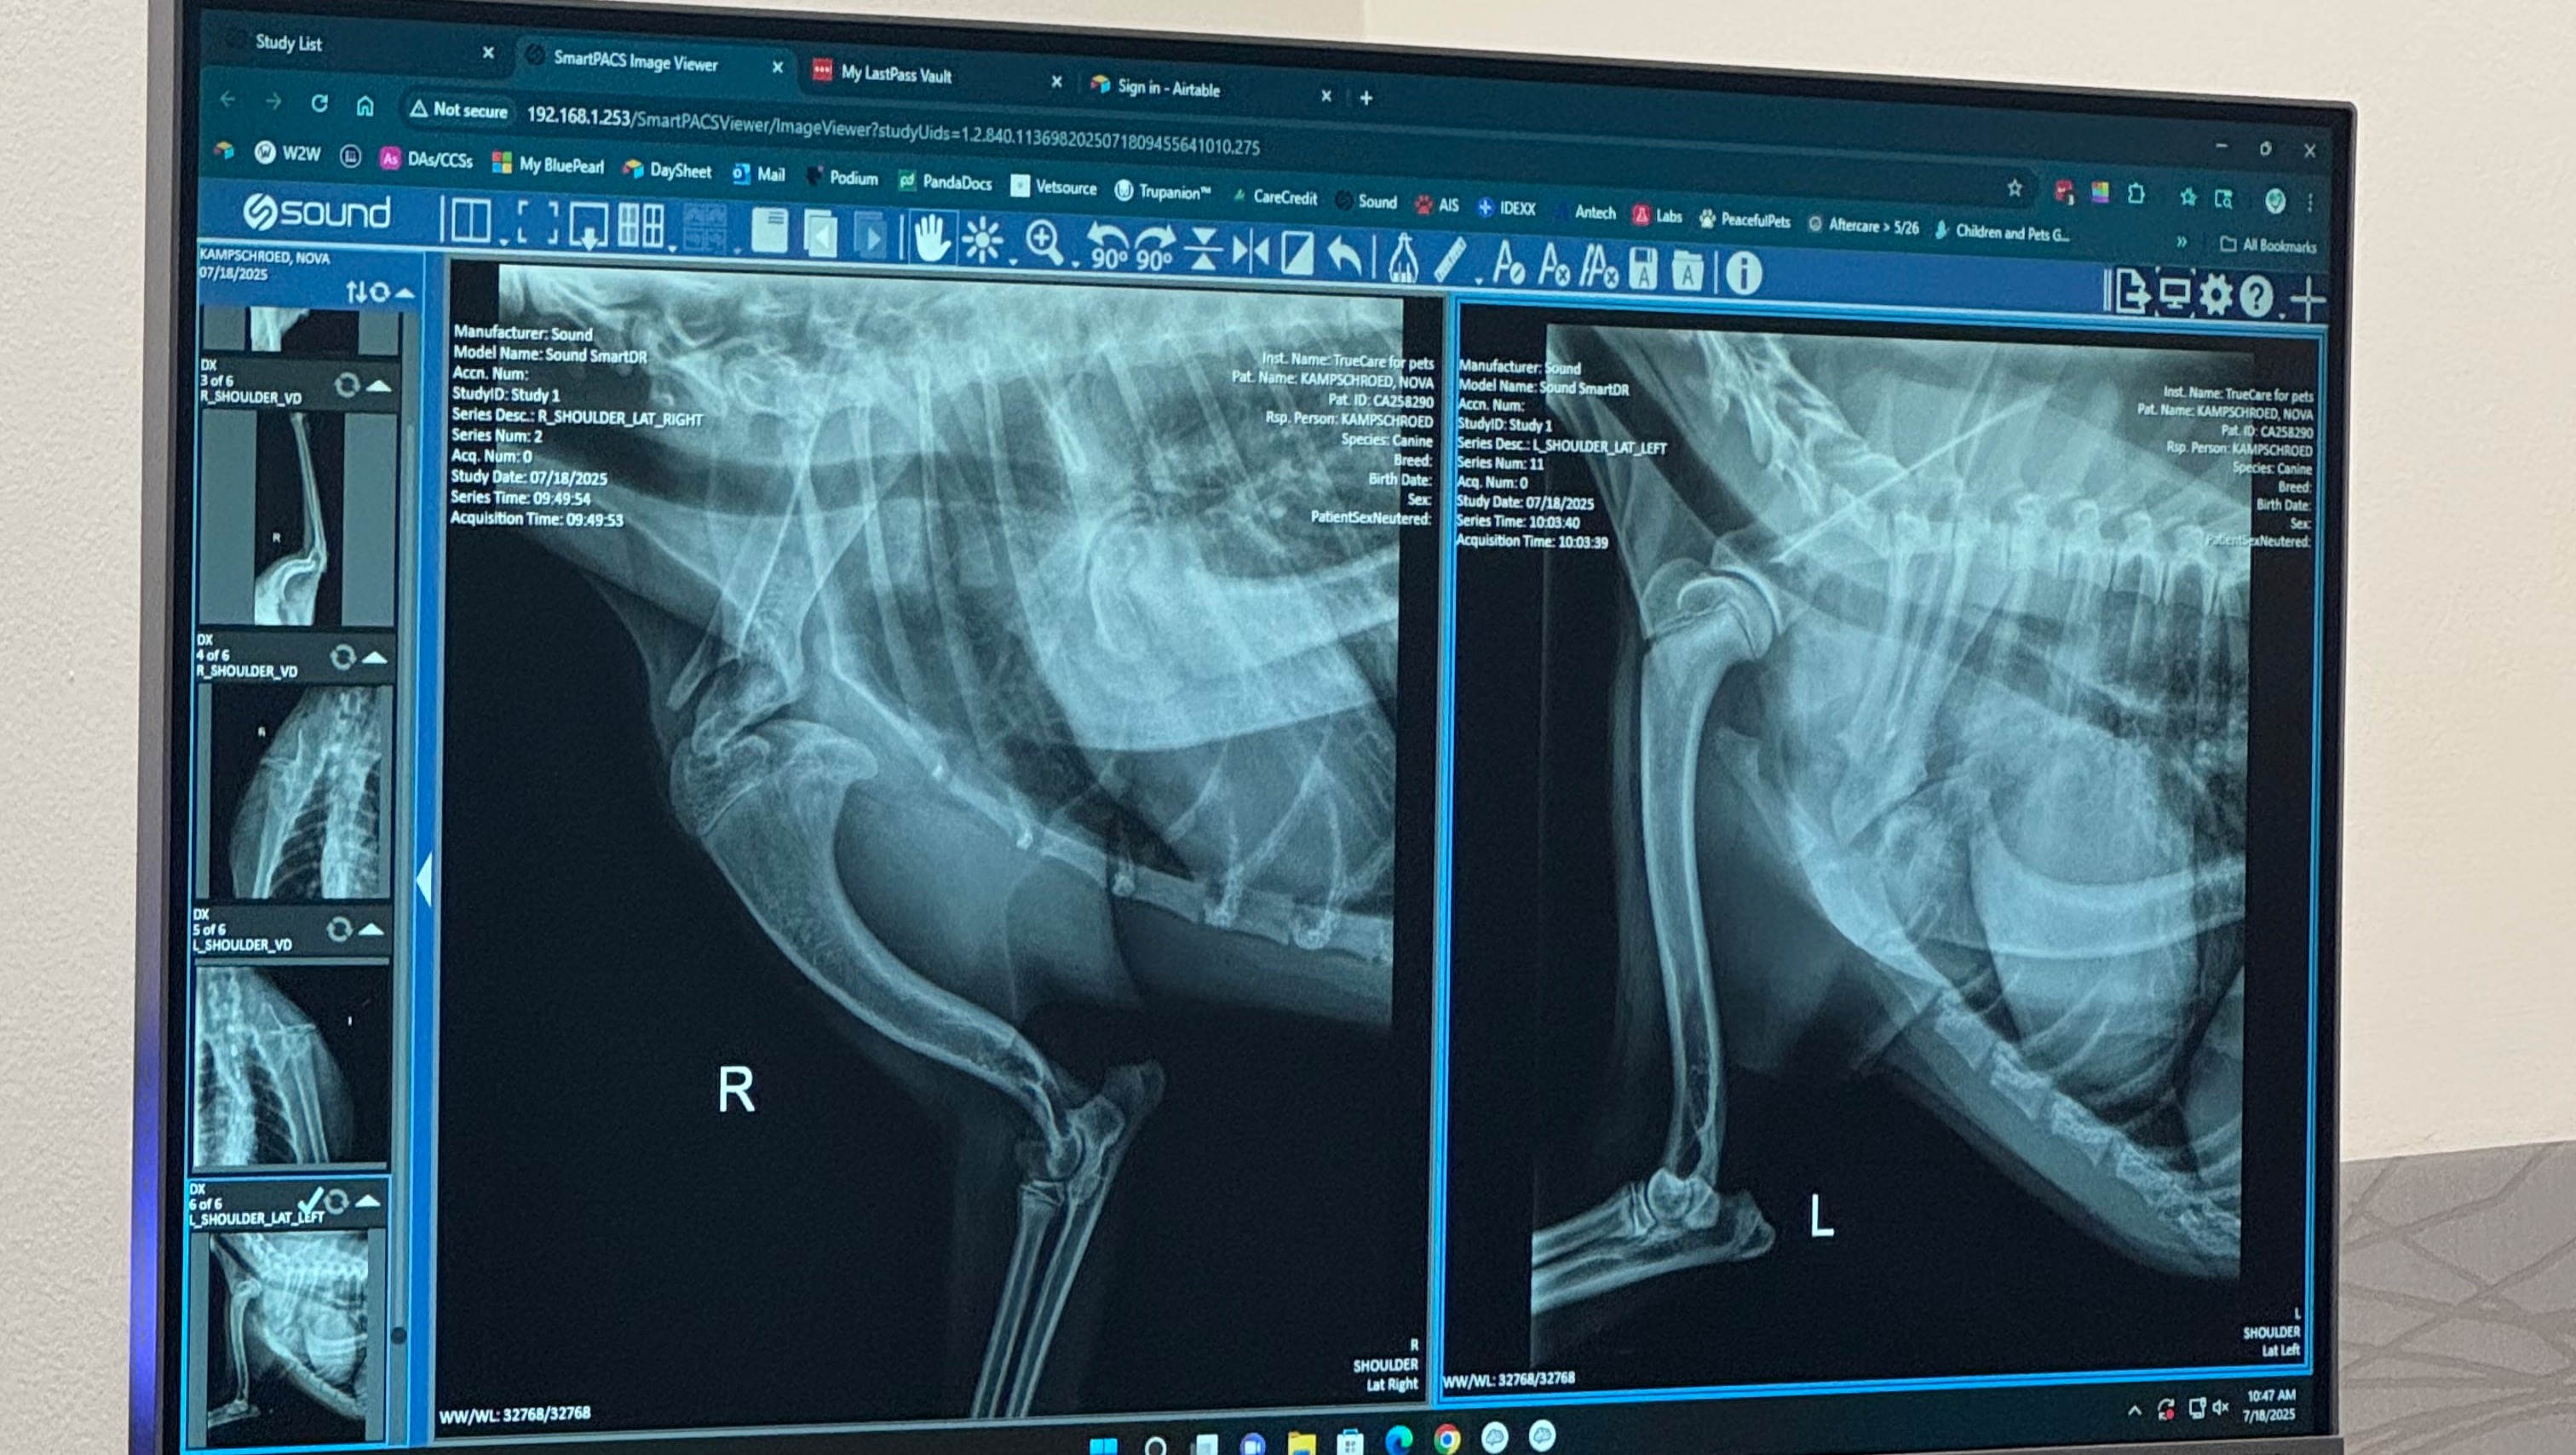

A few months ago, my parents noticed I was limping after playtime. What we hoped was just a minor sprain turned out to be something much more serious. After several vet visits, a general surgeon consult, and a visit with a bone and joint specialist, we learned that I was born with a rare congenital issue: my shoulder joint didn’t form properly (see X-ray attached). That’s why I limp—because my shoulder is basically stuck and can’t move like it should.